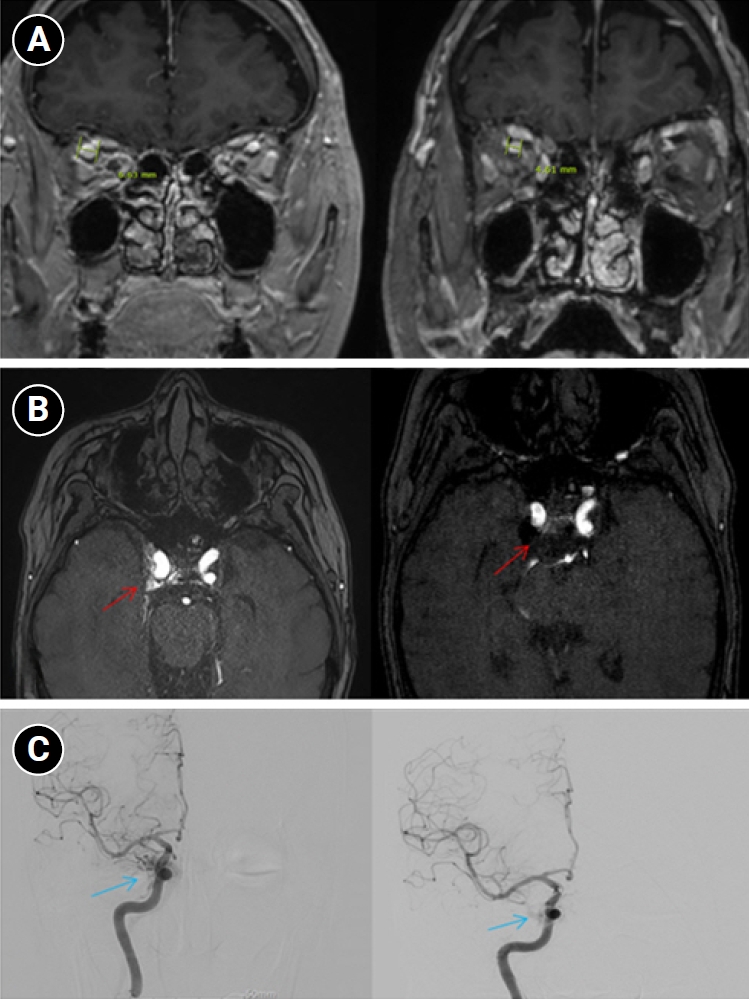

Baseline hematology and chemistry—including complete blood count, electrolytes, renal/hepatic indices—and coagulation tests (prothrombin time/international normalized ratio, activated partial thromboplastin time) were within reference limits. Erythrocyte sedimentation rate and C-reactive protein were normal. A focused screen for secondary trigeminal neuropathy (thyroid-stimulating hormone, vitamin B12, HbA1c) was negative. There were no clinical signs of infection. Brain magnetic resonance imaging (MRI) demonstrated high flow related signal in the right cavernous sinus and asymmetric dilation of the superior ophthalmic veins (right>left), raising suspicion for a CCF (Figure 1). Definitive diagnosis was established on digital subtraction angiography (DSA), which identified a right CCF. DSA demonstrated an indirect CCF supplied by the right meningohypophyseal trunk of the ICA and by right ECA branches, including the internal maxillary artery and the cavernous branch of the middle meningeal artery, consistent with Barrow type D (Figure 2).6 Barrow type D denotes an indirect, low-flow fistula with dual ICA/ECA dural supply; unlike direct type, indirect types present more insidiously, and symptom patterns are largely determined by venous drainage, with posterior drainage often manifesting as CN VI palsy and headache (Table 1).1,3,6,7 The fistula was treated with transvenous Onyx embolization. On post-procedure day 1, non-contrast time-of-flight magnetic resonance angiography (TOF-MRA) demonstrated a marked reduction of flow related hyperintensity within the right cavernous sinus, and the right superior ophthalmic vein caliber decreased from 6.63 to 4.61 mm (Figure 3A, B). Follow-up DSA (at 3 weeks) likewise showed substantial attenuation of fistulous opacification (Figure 3C), supporting a significant interval decrease in arteriovenous shunting. At 1–2 weeks, the patient reported an ~80%–90% reduction in dental/lower-facial pain and bifrontal headache from NRS 7–8 to 1–2. By 1 month, red-glass testing demonstrated resolution of primary-position diplopia. Formal prism measurements were unavailable; bedside ocular-motor grading was recorded using a standard duction underaction scale (–4 to 0). Right abduction improved from –1 to 0, and primary-position diplopia was absent at distance and near, consistent with recovery from abducens palsy.

According to prior literature, posteriorly directed, high-pressure venous drainage in indirect CCFs can precipitate venous congestion around Meckel’s cave, providing a substrate for V2/V3 territory pain; this builds on earlier evidence implicating vascular compromise at the trigeminal (Gasserian) ganglion level.4,5 In our case, the post-procedure reduction in TOF-MRA flow related signal, along with decreased superior ophthalmic vein engorgement, indicates reduced cavernous venous pressure, plausibly relieving congestion around Meckel’s cave and thereby improving V2/V3 pain. The bifrontal, pressure-like headache with nausea/vomiting can be explained by posteriorly directed venous outflow from the fistula, which produces venous hypertension in the cavernous sinus and posterior dural venous pathways.1,3,7 Resultant venous engorgement distends pain-sensitive dura and activates trigeminal meningeal afferents, yielding a secondary dural headache rather than a primary migraine phenotype; the bifrontal topography is compatible with referral from the anterior cranial fossa/cavernous region dura via the ophthalmic and maxillary divisions.1,7 In line with this mechanism, headache occurs more often in indirect CCF than in direct CCF, reflecting posterior venous drainage and dural venous hypertension. Correspondingly, headache improvement tracked with the post-embolization decrease in shunt on TOF-MRA, supporting a venous-driven mechanism linked to posterior drainage. Likewise, abducens palsy—given the nerve’s central course through the cavernous sinus and vulnerability near Dorello’s canal—would be expected to improve as cavernous venous hypertension resolves, consistent with the observed normalization of right abduction on bedside duction grading.

In indirect CCFs as in our patient, endovascular therapy was selected as first-line; if endovascular access is not achievable or durable occlusion cannot be obtained, surgical management may be required.2,3 Given the indirect (Barrow D) angio-architecture, a transvenous approach—typically via the inferior petrosal sinus or, if inaccessible, the superior ophthalmic vein—was preferred, as transarterial embolization of dural feeders in indirect CCFs is associated with a higher embolic stroke risk.6,7 Transvenous embolization is commonly favored for indirect CCFs given the relatively straightforward venous anatomy, and high angiographic occlusion rates have been reported. Overall, endovascular treatment across techniques and access routes yields clinical improvement in approximately 60%–95% of cases.10 Post-embolization TOF-MRA demonstrated a marked reduction of flow related signal in the right cavernous sinus with decreased superior ophthalmic vein engorgement, consistent with interval shunt reduction and accompanied by ~80%–90% relief of dental/facial pain and improvement in diplopia. As shunt flow decreased, the V2/V3 territory pain improved in parallel, supporting the fistula as the proximate source of the pain.

Figure 3.Imaging changes before and after embolization. (A) Brain magnetic resonance imaging (coronal section through the orbits) shows a decrease in the diameter of the right superior ophthalmic vein from 6.63 mm pre-embolization to 4.61 mm post-embolization, indicating reduced venous congestion. (B) Axial time-of-flight magnetic resonance angiography demonstrates that flow-related hyperintensity within the right cavernous sinus is markedly reduced after embolization (red arrows), consistent with decreased shunt flow. (C) Digital subtraction angiography images before embolization show abnormal early pericavernous venous filling along the right cavernous sinus region (blue arrows), compatible with carotid-cavernous shunting. On follow-up, this abnormal filling is no longer visualized, consistent with interval reduction in shunt flow.